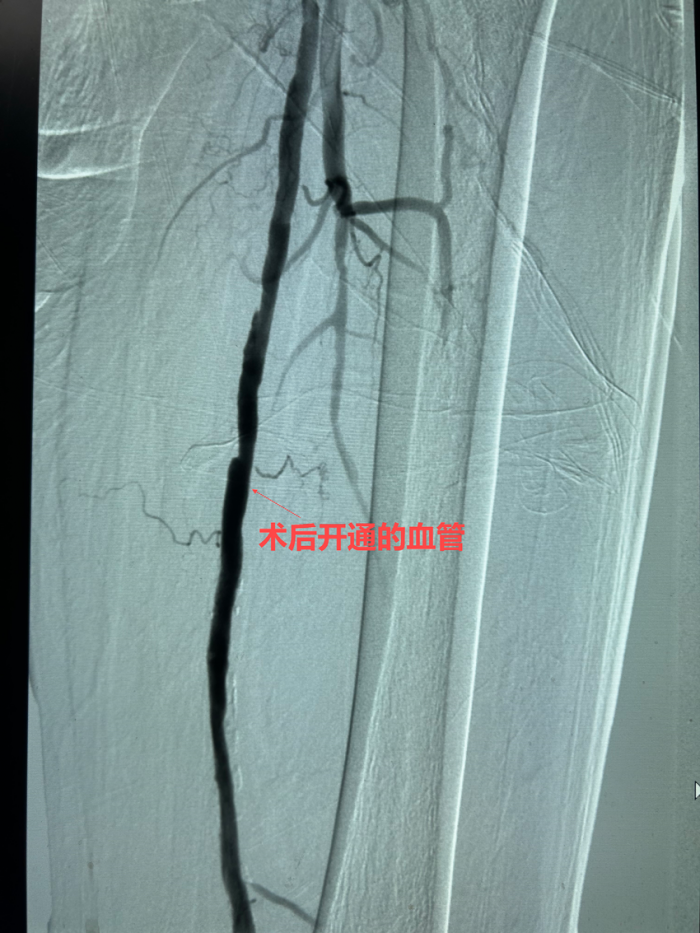

手术当天,紧张的气氛弥漫在手术室。医生们通过股动脉穿刺,小心翼翼地将栓塞保护伞导入腘动脉,这一“保护伞”如同忠诚的卫士,准备兜住旋切过程中脱落的小斑块。在左股动脉中断,斑块旋切术正式开始。手术器械如同微型“刨子”,在直径仅几毫米的血管腔内辗转腾挪。医务人员凭借着精湛的技术,多次调整不同方向进行旋切刨吸。每一次切割都犹如在钢丝上行走,切得太薄无法达到治疗效果,切得太厚则可能损伤脆弱的血管。经过近两个小时的艰苦奋战,手术团队终于成功地将斑块切除并取出,随后药物球囊顺利扩张狭窄血管,抑制内膜增生,确保下肢动脉血流畅通。

术后立见成效,患者重获行走自由